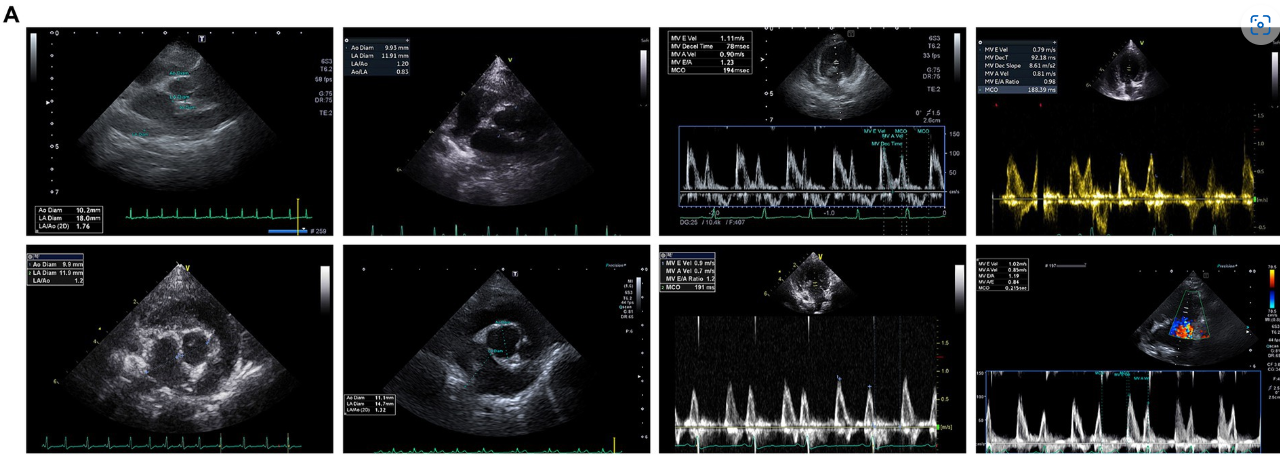

Al inicio del estudio, no se observaron diferencias estadísticamente significativas en los parámetros ecocardiográficos y radiográficos entre el grupo MSC y el grupo control (Tabla 3). Los cambios en los parámetros ecocardiográficos se calcularon restando las mediciones basales de las mediciones de los puntos finales. El grupo control demostró un deterioro estadísticamente significativo en la LA (p = 0,0078), la relación LA/AO (p = 0,0117), la LVIDDN (p = 0,0098), la velocidad E (valor p = 0,0391) y la VHS (p = 0,0312) desde el inicio hasta el punto final a intervalos anuales. Por el contrario, el grupo de terapia MSC no mostró cambios significativos en las mediciones ecocardiográficas durante el mismo período. Aunque no fue estadísticamente significativo, el grupo MSC mostró una mejora en la LA y la velocidad E (Tabla 4). En la Figura 2A se presentan las características ecocardiográficas de las MSC y de los grupos control. Un paciente en el grupo MSC mostró una disminución en la AI de 18 mm a 11,9 mm después del tratamiento con células madre mesenquimales, con una mejor relación LA/AO de 1,8 a 1. Además, el E-peak mejoró de 1,1 m/s a 0,8 m/s. Para un paciente en el grupo de control, la AI aumentó de 11,9 mm a 14,7 mm en un intervalo de 1 año, y la relación LA/AO progresó de 1,2 a 1,3. Además, el pico E empeoró de 0,9 m/s a 1 m/s. Las comparaciones se establecieron restando los valores basales de los valores finales de cada parámetro, y se realizaron evaluaciones ecocardiográficas a intervalos anuales (Tabla 5). Los cambios en los valores se calcularon restando las mediciones de referencia de las mediciones de punto final. Para el diámetro del LA, se observaron diferencias con -0,48 ± 2,86 mm en el grupo MSC y 2,97 ± 2,38 mm en el grupo control (p < 0,05) (Figura 2B). En cuanto a la velocidad E, los cambios fueron de -0,08 ± 0,16 m/s en el grupo MSC y de 0,26 ± 0,30 m/s en el grupo control (p < 0,05) (Figura 2C).

Figura 2. Análisis comparativo de los cambios ecocardiográficos en el MSC y en los grupos control. Comparación de los cambios en la ecocardiografía entre el criterio de valoración y el basal en el MSC y en los grupos control (A). El paciente A1 demostró una mejoría de 18 mm a 11,9 mm en el diámetro de la AI antes (basal) y después (final) del tratamiento con células madre, respectivamente, con una disminución del pico E de 1,1 m/s a 0,8 m/s después del tratamiento. Por el contrario, el paciente B3, parte del grupo control, mostró un aumento en el diámetro de LA de 11,9 mm a 14,7 mm después de 1 año, con un aumento de la velocidad E de 0,9 m/s a 1 m/s. Los cambios en el diámetro de la aurícula izquierda entre el punto final y el basal después del tratamiento con MSC derivadas del tejido gonadal canino, mostraron diferencias de 0,48 ± 2,86 mm en el grupo MSC y 2,97 ± 2,38 mm en el grupo control, lo que indica una diferencia estadísticamente significativa (p < 0,05) (B). Los cambios en la velocidad E entre el punto final y el basal después de la terapia con MSC derivadas del tejido gonadal canino, con los cambios en la velocidad E de -0,08 ± 0,16 m/s en el grupo MSC y 0,26 ± 0,30 m/s en el grupo control, mostrando una diferencia estadísticamente significativa entre ellos (p < 0,05) (C). *P < 0,05.